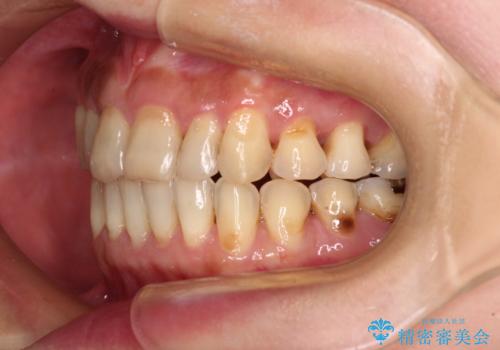

マウスピース矯正は、奥歯が常にマウスピースを介して咬み合うため、治療過程において前歯のみが接触して奥歯が咬み合わないということが頻発します。

元々奥歯の咬み合わせに問題のある方の場合、治療期間が長期化したり、咬み合わせの改善ができなかったりすることがあります。

マウスピースのみでは治療を終了させることができなくなり、ワイヤー矯正を併用したり、顎間ゴムを多用したりといった対応が必要となります。